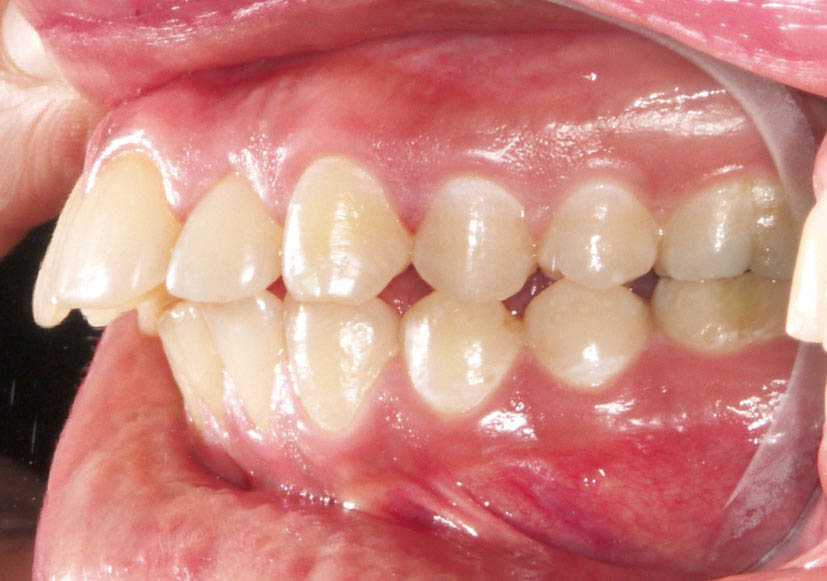

شکل 97-2: مرتب بودن دندانهای قوس پایین و طرح درمان غیر کشیدنی آن

شکل 98-2: اکلوژن کلاسI در سمت چپ

شکل 99-2: اکلوژن کلاسI در سمت راست